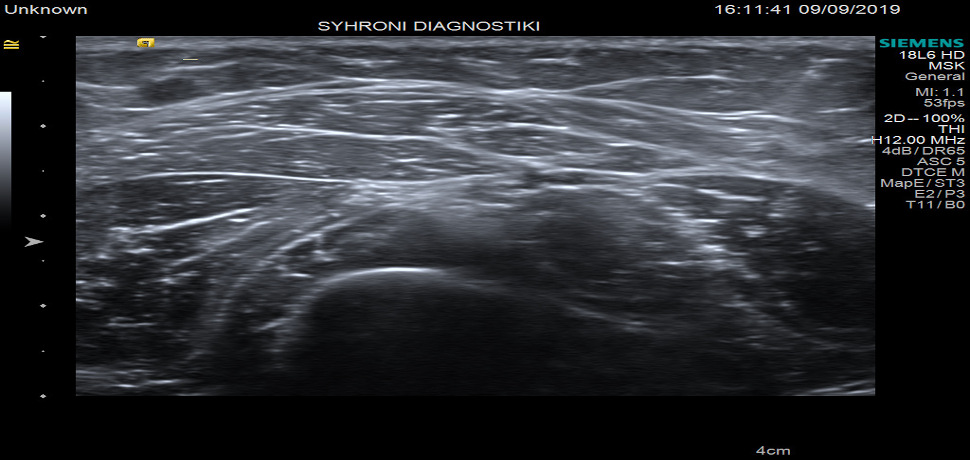

Με το υπερηχογράφημα μαστού είναι δυνατή η λεπτομερής απεικόνιση των μαστών και των μασχαλιαίων κοιλοτήτων ετσι είναι δυνατή η ανάδειξη και συναξιολόγηση βλαβών( που ανακαλύπτονται είτε με την κλινική εξέταση είτε με τη μαστογραφία).Επίσης μπορεί εύκολα να διαχωρίσει συμπαγή από κυστικά μορφώματα και να αναγνωρισει τους καλοηθεις από τους κακοήθεις μασχαλιαίους λεμφαδενες.

Στο ιατρείο χρησιμοποιειται το σύστημα Siemens S1000 HELX με ηχοβολέα υψηλής ευκρινιας για την εξέταση του μαστού.